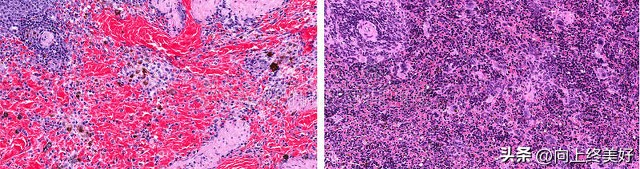

病理学与病理生理学是研究疾病发生和发展的科学,包括疾病发生的原因、过程和结果。病理学主要关注疾病发生后的形态学变化,而病理生理学更关注疾病过程中的功能变化和体内各个系统的反应。